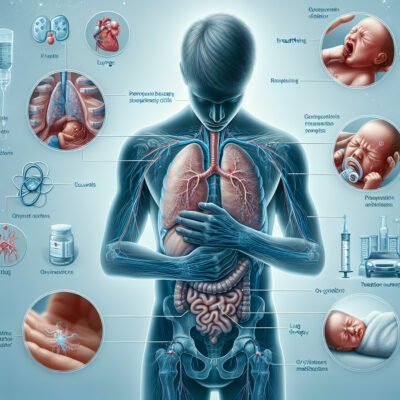

Респіраторний дистрес синдром: Що це таке?

Респіраторний дистрес синдром — це особлива бяка, що робить дихання мукою. Це жах реально може зламати життя новонародженим, і взагалі будь-кому, хто схильний до дихальних проблем. Коротше кажучи, це коли легені підводять тебе, не даючи нормально дихати. І зовсім неподалік проблема з киснем. Грубо кажучи, RDS (Respiratory Distress Syndrome) може виникнути раптом. І як із цим жити — інше питання.

Симптоми, які слід знати

Добре, поговоримо про те, що може викликати занепокоєння. Якщо ви помітили щось таке:

- Швидке, важке дихання.

- Синюшний відтінок шкіри. Не найкращий гламурний відтінок.

- Хрипи. Не те щоб симфонія.

- Зниження здатності до контакту. Ви ніби тут, але ніби й не тут.

Способи лікування

Не все так похмуро, є способи справитися з цим жахом:

- Кисневий режим: щоб повернути баланс.

- Механічна вентиляція: коли свої легені відмовляються працювати.

- Сурфактантна терапія: спеціально для малюків.

Можливі ускладнення

На жаль, РДС може тягнути за собою такі капості:

- Інфекції легень, через які життя може стати парою днів в тумані.

- Хронічні проблеми з легенями. Ви не завжди зможете їх перечекати.